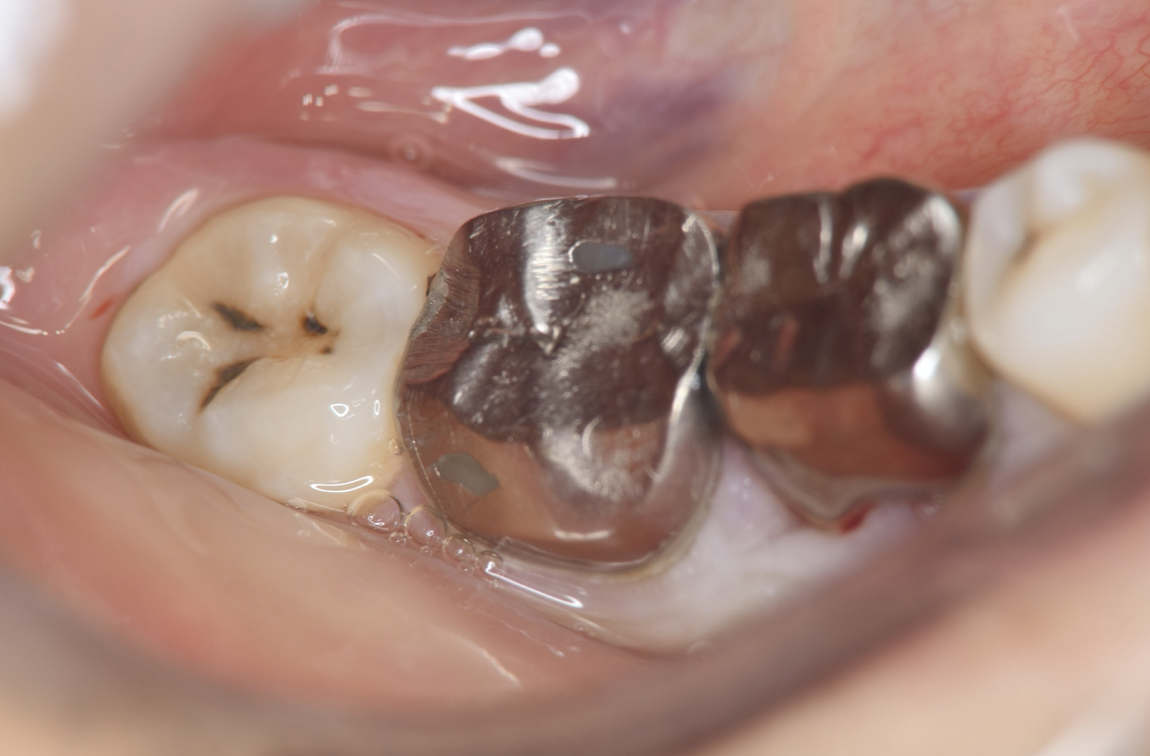

A 27-year-old female patient came to us with discomfort in the right lower jaw (Figure 1). Her primary symptoms were pain in the lower right tooth when biting and discomfort associated with not being able to chew well with the lower left single denture. The patient was married and had one young child, and previously received dental treatment in China, then had returned to Japan for childbirth and early childcare. The patient was a nonsmoker with moderate plaque control and medical history taking revealed no problems. In clinical and radiographic examinations, a root fracture was observed on tooth #46, which had been endodontic ally treated and restored with a full-cast metal crown. Periodontal probing revealed a pocket depth of 8 mm on the buccal center side of the tooth. No pain was detected with percussion and mobility of the tooth was normal. (Figure 1, Figure 2, Figure 3).

Figure 3.Preoperative intraoral findings. A metal crown was inserted at #46 and bleeding on probing during the periodontal pocket examination was noted.